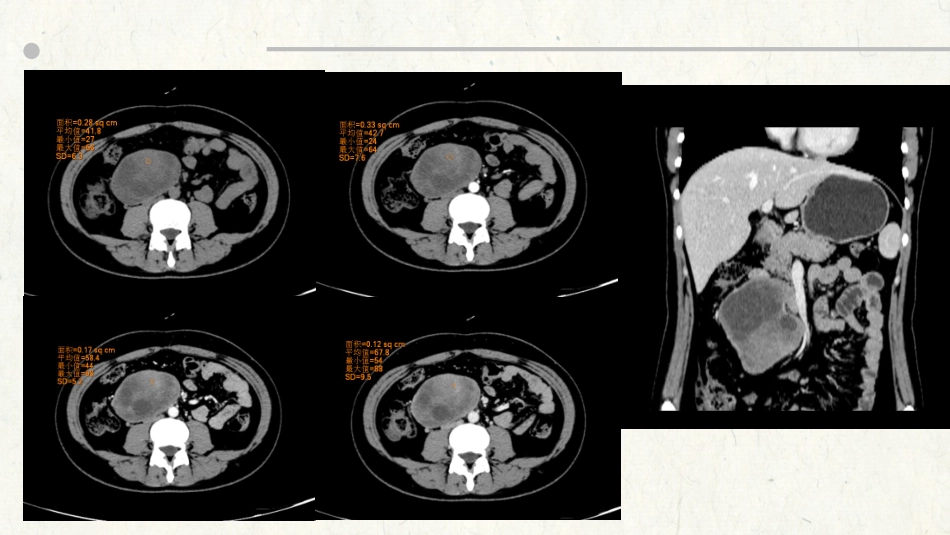

病例随访腹膜后神经鞘瘤腹膜后神经鞘瘤起源于周围神经的施万细胞,故好发于脊柱旁、肾脏内侧和盆腔骶前区等神经组织丰富的部位,与腰大肌及髂腰肌关系密切;发生于腹膜后的神经鞘瘤少见,发病率占腹膜后肿瘤的0.3%~6.0%。腹膜后神经鞘瘤可发生于任何年龄,好发于20~50岁,无明显性别差异。概述临床上因肿瘤生长缓慢,起初一般无症状,多数患者以无痛性肿块就诊,或体检时发现,当肿瘤生长到一定程度压迫神经时,可出现腹痛、腰背痛及下肢放射痛或酸胀麻木感,病沿神经分布出现触电感,肿瘤若侵犯邻近器官出现血尿、骨痛等症状,则考虑为恶性神经鞘瘤,位于盆腔的肿瘤可同时压迫直肠和尿道,引起排便、排尿困难。临床特点腹膜后神经鞘瘤的CT及MR平扫特征:CT表现为类圆形、圆形肿块,有完整包膜,边界清楚,瘤体较大者可见坏死、囊变区,囊变、坏死、钙化是腹膜后神经鞘瘤的表现之一;MRI平扫肿块T1WI及T2WI信号均不均匀,T1WI呈低及稍低信号;T2WI信号为高低混杂信号,DWI呈高信号;腹膜后神经鞘瘤增强扫描特征:神经鞘瘤典型的强化方式为进行性延迟强化,可以均匀或不均匀强化;影像特点神经鞘瘤影像征象与病理学特点关系密切,大体病理观察,腹膜后神经鞘瘤多呈圆形或卵圆形,表面多光滑,包膜完整;切面灰白或灰黄色,很少发生钙化。镜下肿瘤内可见AntoniA区和AntoniB区2种组织类型。AntoniA区细胞成分较丰富,排列密集,细胞境界不清;AntoniB区细胞排列较疏松,呈网状结构,细胞间有较多液体存在,易发生黏液变、囊变或出血。影像特点与病理AntoniA区与B区可并存于一个肿瘤内,也可单独存在,AntoniA区CT多为较高密度,MR上,AntoniA区T1WI与肌肉等信号,T2WI上信号较肌肉略高,一般为富血供区,呈中等程度以上强化,AntoniB区CT多为水样低密度,MRT1WI上为低信号,T2WI上为显著高信号,一般为少血供,强化不明显。此外,肿瘤纤维含量也影响T2WI信号强度,富纤维区域T2WI信号偏低,动态增强强化不明显。影像特点与病理鉴别诊断腹膜后神经源性肿瘤神经鞘膜来源交感神经节细胞来源副神经节瘤神经鞘瘤神经纤维瘤神经节细胞瘤神经节母细胞瘤神经母细胞瘤功能性无功能性副神经节瘤(paraganglioma,PGL)为较少见的腹膜后肿瘤,占腹膜后肿瘤的1%~3%,发病年龄约为40岁,起源于神经嵴细胞,部分肿瘤可分泌儿茶酚胺,临床上根据有无分泌功能分为功能性PGL和无功能性PGL。肿瘤多为实性或囊实性,圆形或类圆形,边缘清楚或欠清,CT平扫主要表现为等或等低混杂密度灶;CT增强扫描动脉期表现为明显均匀或不均匀强化的软组织肿块,肿瘤周围或瘤内可见粗大的血管,局部强化程度可接近于血管。静脉期强化程度趋向于较动脉期均匀,密度较动脉期略下降。副神经节瘤左侧腹膜后副神经节瘤,CT平扫是囊实性肿块,内见斑点状钙化,增强动脉期实质明显强化,病灶周边见扭曲增粗的血管影,静脉期实质强化减退;副神经节瘤节细胞神经瘤(ganglioneuroma,GN)起源于交感神经节的原始神经嵴细胞,是一种周围神经良性肿瘤,临床比较少见。所有年龄均可以发病,以儿童和青壮年为主。肿瘤沿交感神经链的任何部位和肾上腺髓质分布,腹膜后及后纵隔是最常见的2个部位。节细胞神经瘤节细胞神经瘤质地较软,多爬行生长或沿器官间隙呈嵌入方式生长,与周围组织分界清楚。当病灶较大时,可不同程度压迫或包绕周围组织、器官及血管,但器官、血管形态基本正常,未见受侵征象,包绕但不挤压血管,推移但不侵犯周围组织,该特点是其重要影像学征象之一。因肿瘤内含大量黏液基质,密度较低,CT上主要表现为低密度肿块,低于同层肌肉密度。增强扫描动脉期无或轻度强化,静脉期、延时期可呈渐进性不均匀缓慢条带状、结节样强化。节细胞神经瘤腹主动脉前方见一不规则的肿块,密度略不均匀,内见点状钙化,增强扫描持续轻度强化,病灶包绕腹腔干等大血管,腹腔干血管形态正常,管壁光滑;节细胞神经瘤小结神经鞘瘤副神经节瘤节细胞神经瘤来源施万细胞神经嵴细胞神经嵴细胞发病年龄20-5040儿童、青壮年病灶形态圆形、类圆形肿块,边界清楚,包膜完整,密度多不均匀实性、囊实性的圆形或类圆形肿块形态不规则,可沿器官间隙呈嵌入式生长强化特点动态增强早期血供不丰富,多呈渐进性强化动...